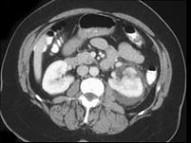

问题 男,48岁,有外伤史,请根据所示图像,选择最可能诊断 ( )

选项 A、左侧肾盂输尿管交界处撕脱伤 B、未见异常 C、左肾裂伤 D、左肾动脉撕裂伤 E、左肾挫伤

答案 C